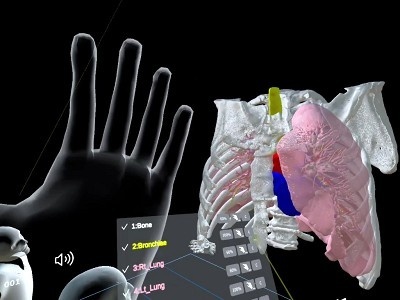

今回の授業ではこの1年間に習った内臓や筋、血管や神経といった臓器がどのように体内に存在し、その内部構造がどうなっているのかを、VR(3次元の仮想空間)で理解していきます。

これまでの授業では、教科書の2次元での説明が主であり、体の中を見ることが出来ない為、なかなか内部構造を理解するのが困難なようでした。

しかし、このVRを用いた授業では、「へえ~」「なるほど」と仮想空間にある臓器を持ったり、位置の確認をしたり、のぞき込んだりと楽しく授業を受けていました

- 胸郭